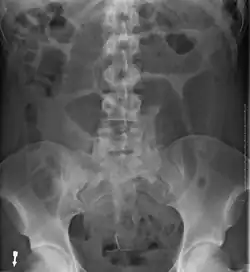

-

Plain X ray of a cecal volvulus -

CT scan of a cecal volvulus